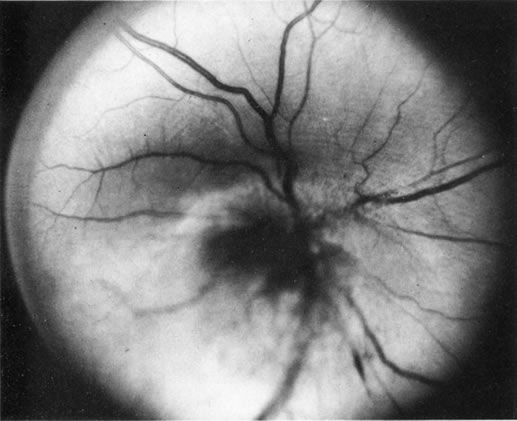

Necrotic melanomas account for approximately 5% of uveal melanomas; in the majority of cases, there is intraocular inflammation accompanying the cataract.7–9Figures 1 and 2 demonstrate a typical case. The patient had a long history of unilateral decreased vision. The eye had become painful 1 month before admission, and he was referred for evaluation of uveitis. Clinically, there was a dense, unilateral cataract with significant intraocular inflammation, which was manifested as a ciliary flush with 2+ cells and flare. Media opacity obscured all fundus detail. An immersion B-scan demonstrated a large intraocular tumor that was most consistent with a uveal melanoma. The eye was removed, and the diagnosis was confirmed histologically.10

Fig. 2. Immersion B-scan of the patient in Figure 1 demonstrates a uveal melanoma.